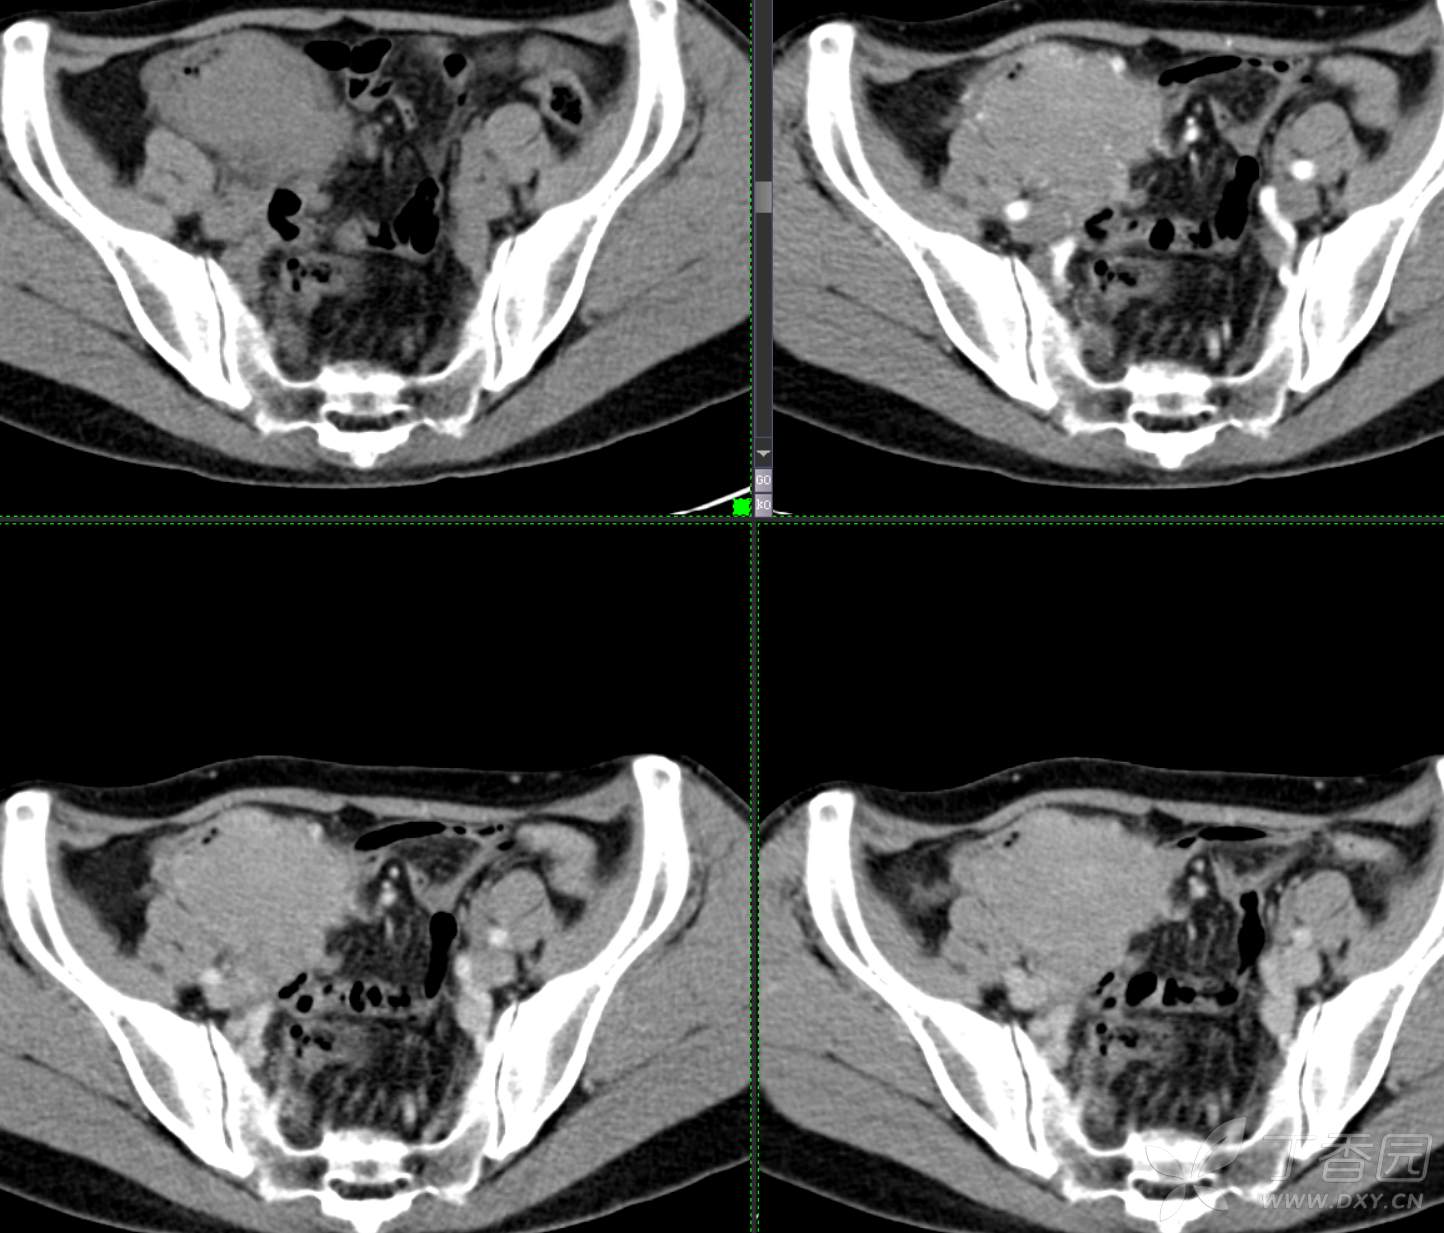

腹组13:患者,女,62岁,大便习惯改变2月余

主 诉: 【大便性状改变2月余】

现病史: 患者2月余前无明显诱因下出现大便次数增多,无明显血便黑便及粘液脓血便,大便次数由1次/日增加至2-3次/日,大便形状变细如小指,偶稀软不成形,无腹痛腹胀腹泻,无恶心呕吐、胸闷气促,肛门排气通畅,无发热盗汗。至当地医院就诊,行肠镜检查发现"回盲部占位"。为进一步治疗,我院门诊拟"回盲部肿瘤"收住入院。